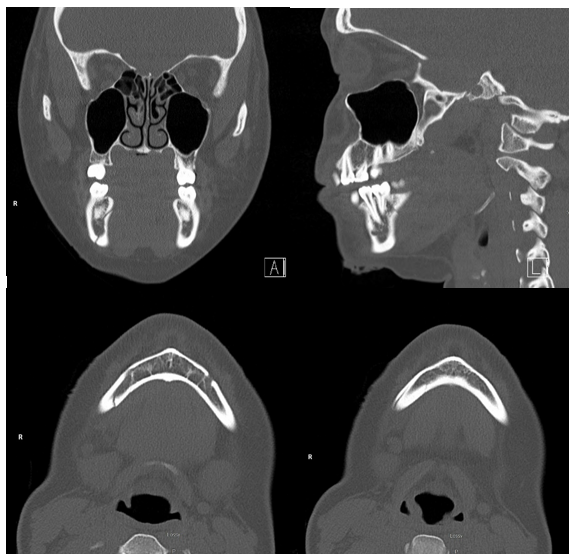

A healthy, non-smoking, 22-year-old woman presented to the emergency department after suffering a fall from her bicycle. She was helmeted and denied any loss of consciousness or neck symptoms. Lower lip and chin lacerations were evident and she reported that her bite did not align. A noncontrast maxillofacial CT was obtained and showed a minimally displaced fracture of the right mandibular body and a minimally displaced fracture of the left mandibular condyle (Figures 1 & 2). Her soft tissues injuries were repaired and she was referred to the otolaryngology clinic for management of her fractures. Two days following the injury, the patient was evaluated in the clinic. She reported pain throughout the mandible in addition to trismus and mild malocclusion. The fractures were discussed and surgical treatment with ORIF and MMF was advised. An informed consent discussion occurred in which the risks and benefits of both the recommended treatment and no treatment were made clear. The patient expressed reasonable reservations about the surgery and opted for non-surgical management only. She was warned of the risks of non-union, malunion, and a potentially prolonged recovery period. Given her choice, she was strongly advised to visit the clinic on a weekly basis, adhere to a slowly progressing diet, and otherwise rest her jaw. The patient presented as mature and reliable and agreed to the plan.

Figure 2 Non-contrast CT. Left to right, top to bottom; coronal, sagittal, and transverse views of the left mandibular condylar fracture.